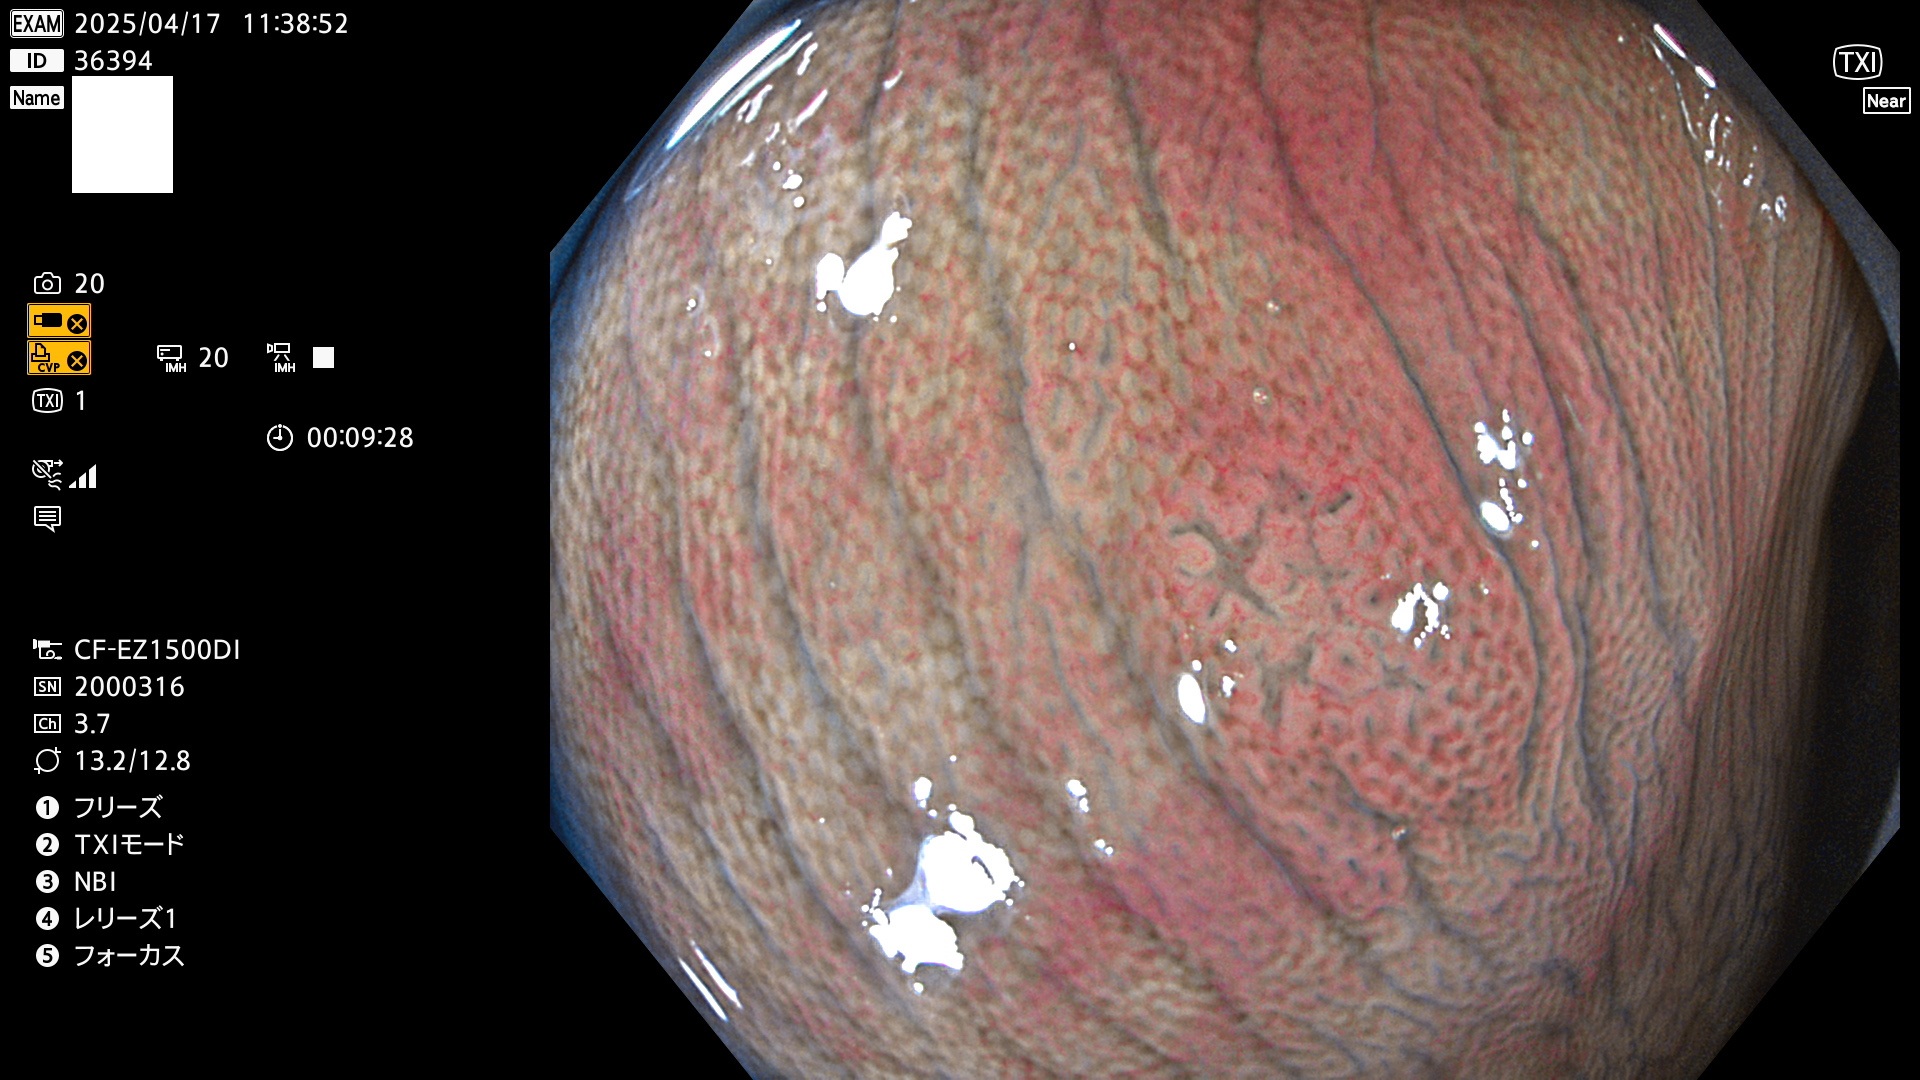

今週のUb、Uc型腺腫

完全に平坦な物をUb、陥凹している物をUcと呼びます。Ubは認識が困難で、Ucはびらん(炎症)と紛らわしいために見落とされやすく、「内視鏡後・大腸癌」の原因になります。

毎週の検査(木・金・土・日)に発見されたUb、Uc型・腺腫を、その週の日曜の夜にUPし1週間、提示します。

抽出の対象期間 2025年4月17日〜4月20日の4日間(48件の検査)8個 (8/48=16%)